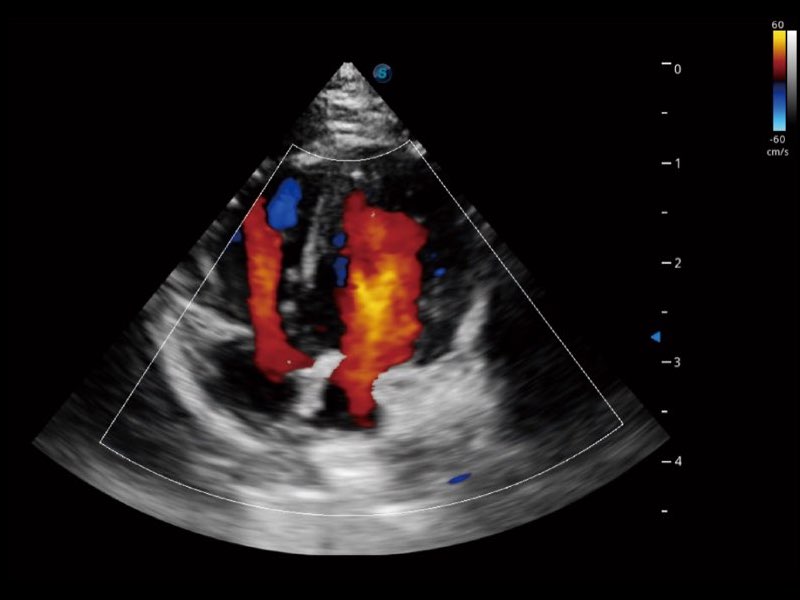

Przy pracach nad aparatem ProPet 60 uwzględniono najważniejsze preferencje i potrzeby weterynarzy, oferując finalnie przystępne cenowo i odpowiednio wyważone połączenie znakomitej precyzji klinicznej, zwiększonej wydajności i przemyślanego przebiegu pracy, niezastąpione w codziennej praktyce weterynaryjnej. Dzięki dostępowi do pełnej gamy głowic HD rozwiązanie to spełnia wszystkie potrzeby w zakresie obrazowania, umożliwiając wykonywanie badań jamy brzusznej, małych narządów, ortopedycznych, badań podczas rozrodu, a nawet badań serca i klatki piersiowej, a to wszystko przy doskonałym stosunku jakości do ceny.